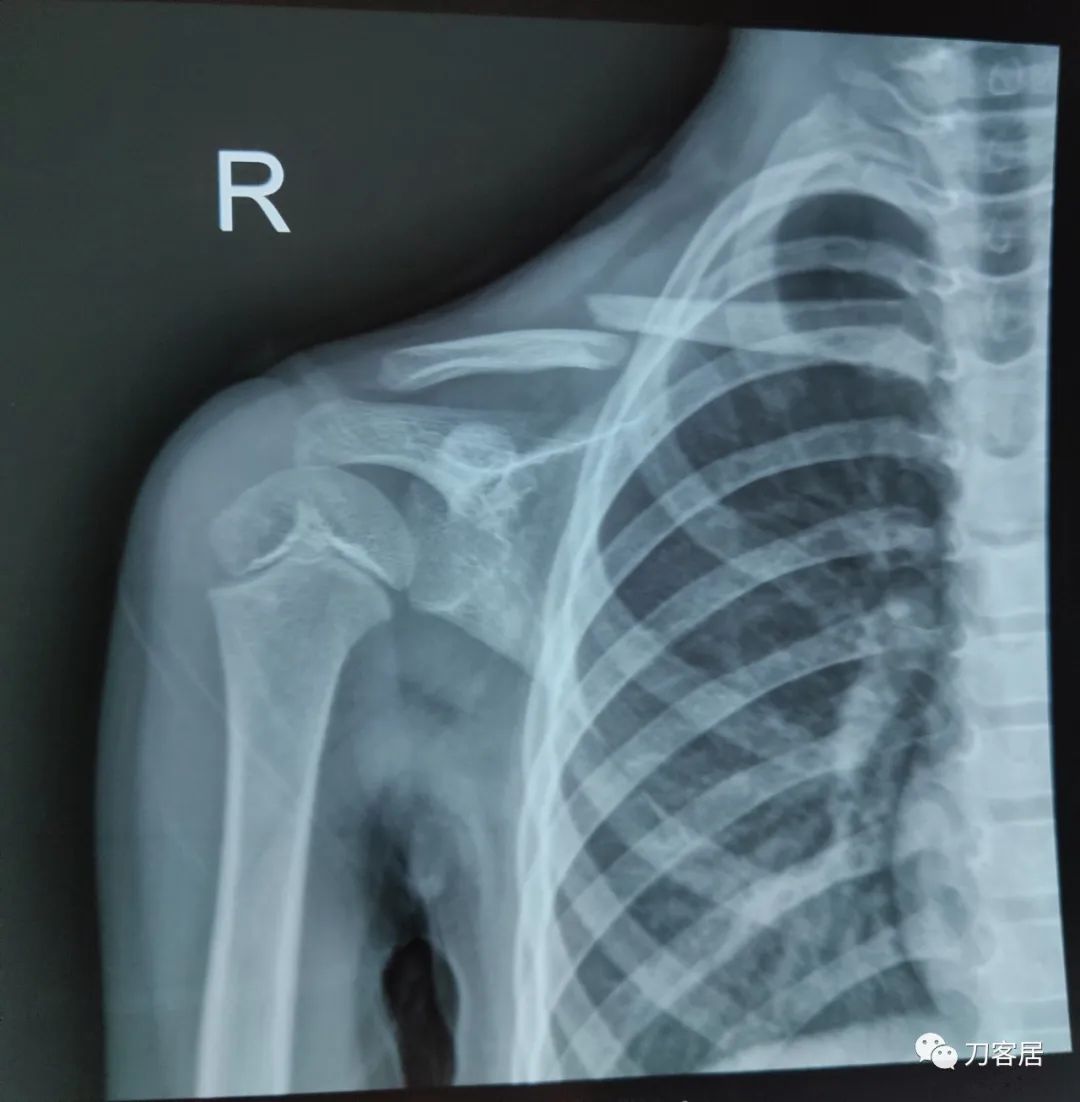

这是今天第二个锁骨保守,7岁,同样8字固定,一个月了,家长不满意。

马老师,前面两个片子是一个5岁女孩的,后面那个片子是一个7岁女孩的,只有一张。